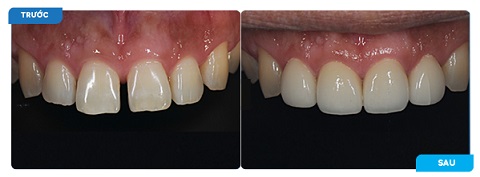

Trám răng thẩm mỹ laser (hoặc trám răng công nghệ halogen quang trùng hợp) là phương pháp trám răng hiện đại với việc sử dụng vật liệu trám là composite nha khoa kết hợp chiếu đèn laser (hoặc chiếu đèn halogen quang trung hợp) để khôi phục các phần răng bị gãy, mẻ, vỡ, lỗ sâu răng hoặc để khắc phục các khuyết điểm cho răng thưa hay răng hở kẽ.

Trám răng thẩm mỹ laser – composite được áp dụng đặc biệt hiệu quả trong những trường hợp: Răng sâu, răng sâu nặng có lỗ sâu khá lớn, răng bị vỡ, răng gãy, răng mẻ, răng có kẽ hở (hở kẽ chân răng), răng thưa nhưng không quá nghiêm trọng.

Tính thẩm mỹ của trám răng laser

Đây chính là đặc điểm ưu việt nhất của trám răng thẩm mỹ laser.

– Chất liệu trám luôn có màu đồng nhất với răng thật (đo màu răng thật rồi mới pha màu composite) và khả năng kháng xuống màu, nhiễm màu giúp răng sau khi trám có màu như răng thật và giữ được màu lâu dài.

– Composite ban đầu là dạng sệt nên việc tạo hình răng sẽ dễ dàng do đó, về mặt hình thể răng cũng giống như răng thật.